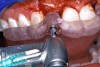

Before the day of surgery, the patient was seen by the orthodontist for the removal of the orthodontic brackets. The patient still was not pleased with the position of the two centrals, and it was determined that this would be addressed after implant placement (Figure 13A). The anatomical variations of the crestal tissue and lack of interdental papilla can be appreciated in the close-up views of the right and left sites (Figure 13B and 13C). There were no surprises on the day of surgery as all of the decisions were made during the planning phase, before the scalpel ever touched the patient. The occlusal view of the CT 3D model revealed the wider alveolar ridge on the right side and thinner crest on the left side (Figure 14A). This was confirmed when the full thickness mucoperiosteal flaps were elevated, and the underyling bone revealed (Figure 14B). The tooth-borne templates were designed to facilitate the drills and drilling sequence specific to the diameters of the predetermined implants (Figure 15A). Each template contained an embedded 5-mm long stainless steel tube, which was approximately 0.2-mm wider than each drill (just wide enough to allow for the drills to rotate freely). Once positioned over the natural teeth, the template was secure and offered precision accuracy in transferring the implant locations from the original software-designed plan, allowing the potential for internal and external irrigation (Figure 15B). The 3.7-mm diameter Tapered Screw-Vent implant drilling sequence requires three drills: pilot, intermediate, and final sizing. Thus, three separate templates were fabricated to a.commodate these sizes. The templates were removed easily and replaced with the next sequential size in less time than it takes to change the drill on the surgical handpiece. After the osteotomies had been.completed, the implants were delivered to the site (Figure 16A and Figure 16B). For this internal hex connection implant, the author r.commends that the flat of the antirotational hex be positioned to the facial for proper orientation of the restorative.components (Figure 17A). Preprepared margins were created from a milled titanium fixture mount transfer post, which was delivered to the implant as support for an immediate transitional restoration. The facial “dot” helped confirm the orientation of the abutment to the facially positioned flat side of the internal hex connection (Figure 17B). Before cementation of the transitional acrylic restorations, a closed-tray, fixture-level impression was made, and a soft-tissue model fabricated.

Figure 15a  A surgical template was derived from the final treatment plan created in the software, which facilitated (A) the drilling sequence and (B) precise location of placement.

Figure 15a

Figure 15b  A surgical template was derived from the final treatment plan created in the software, which facilitated (A) the drilling sequence and (B) precise location of placement.

Figure 15b